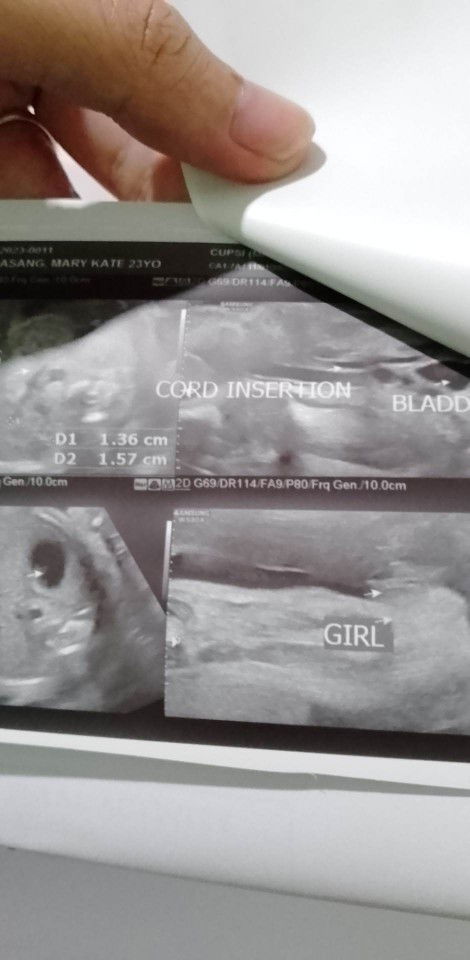

Hello mga mommies, antukin din po ba kayo ngayong buntis kayo or noong preggy pa? Kasi malapit na ako sa 3rd tri pero grabe yung antok ko iba talaga ang tulog sa umaga kaysa sa gabi. Nakakapagod kasi nangangalay na ako kaya kahit maaga pa lang highblood na 😅. Nag stretching naman ako at konting hike muna pero ang sarap po talagang matulog. Pag 3rd trimester po ba pwede pa ring matulog kahit anong oras? Sabi kasi nila baka mahirapan ako sa panganganak if laging natutulog. Thank you! Btw, share ko lang ang good news. It's a girl! 🥳

mommy of baby Rya ❤️